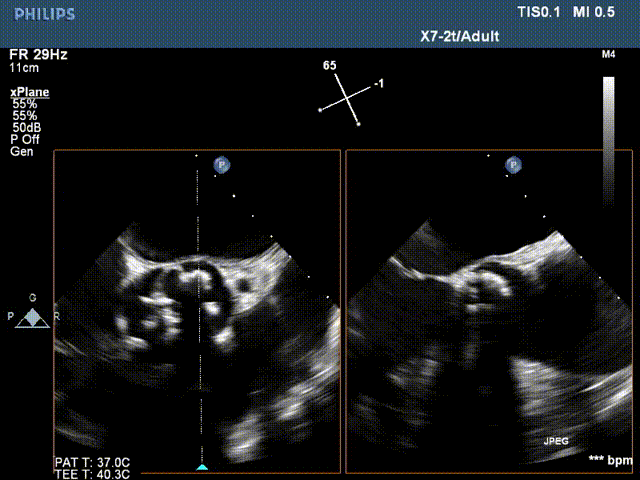

术前超声评估:

术后超声提示瓣周12点位(左右窦交界处)可见一束返流,容积1.0ml,支架前、后缘距主动脉瓣环约4-5mm,固定良好,瓣叶启闭正常。